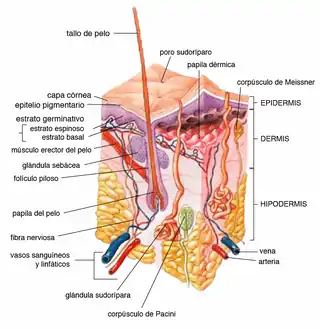

El tejido subcutáneo (del latín subcutaneous "debajo de la piel"), también llamada hipodermis, hipodermo (del griego "debajo de la piel"), tejido subcutáneo, fascia superficial,[1] es la capa más baja del sistema tegumentario en los vertebrados.[2] Los tipos de células que se encuentran en la capa son fibroblastos, células adiposas y macrófagos. El tejido subcutáneo se deriva del mesodermo, pero a diferencia de la dermis, no se deriva de la región del dermatoma del mesodermo. Consiste principalmente en tejido conectivo laxo y contiene vasos sanguíneos y nervios más grandes que los que se encuentran en la dermis. Es un sitio importante de almacenamiento de grasa en el cuerpo.

Estructura

- Bandas fibrosas que anclan la piel a la fascia profunda[3]

- Fibras de colágeno y elastina que lo unen a la dermis

- La grasa está ausente de los párpados, el clítoris, el pene, gran parte del pabellón auricular y el escroto[4]

- Vasos sanguíneos en ruta hacia la dermis

- Vasos linfáticos en ruta desde la dermis

- La parte glandular de algunas glándulas sudoríparas; glándula mamaria se encuentran completamente dentro del tejido subcutáneo[5] (que son glándulas sudoríparas apocrinas modificadas)[6]

- Nervios cutáneos y terminaciones libres

- Raíces del folículo piloso

- Corpúsculos de Pacini y de Ruffini[7]

- Mastocitos[8]

- Bolsas, en el espacio que recubre las articulaciones para facilitar el paso suave de la piel suprayacente

- Hojas finas y planas de músculo, en ciertos lugares, incluido el cuero cabelludo, la cara, la mano, el pezón y el escroto, llamado panículo carnoso